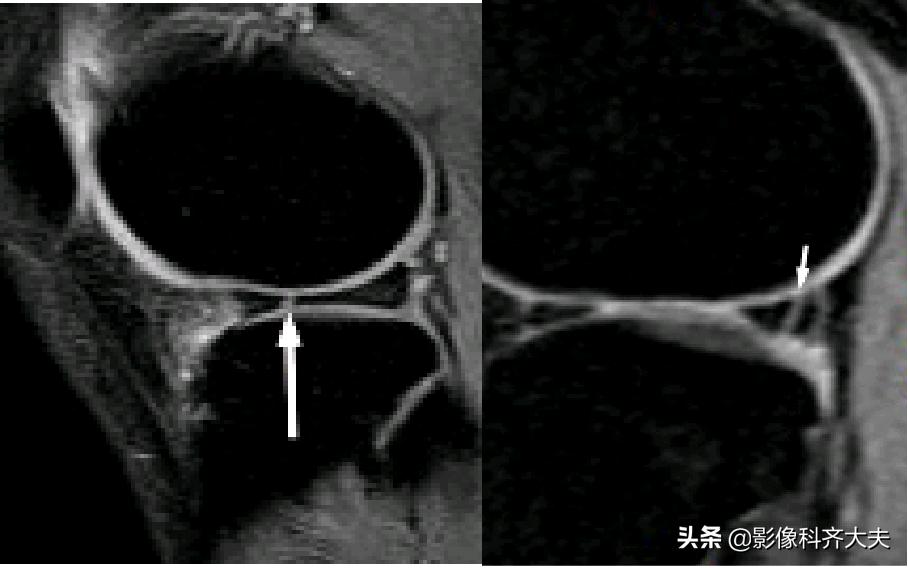

容易误诊为半月板损伤的正常解剖结构

膝横韧带:

腘肌腱腱鞘:

后股板韧带:

关节内气体伪影:

内侧半月板后角上隐窝: